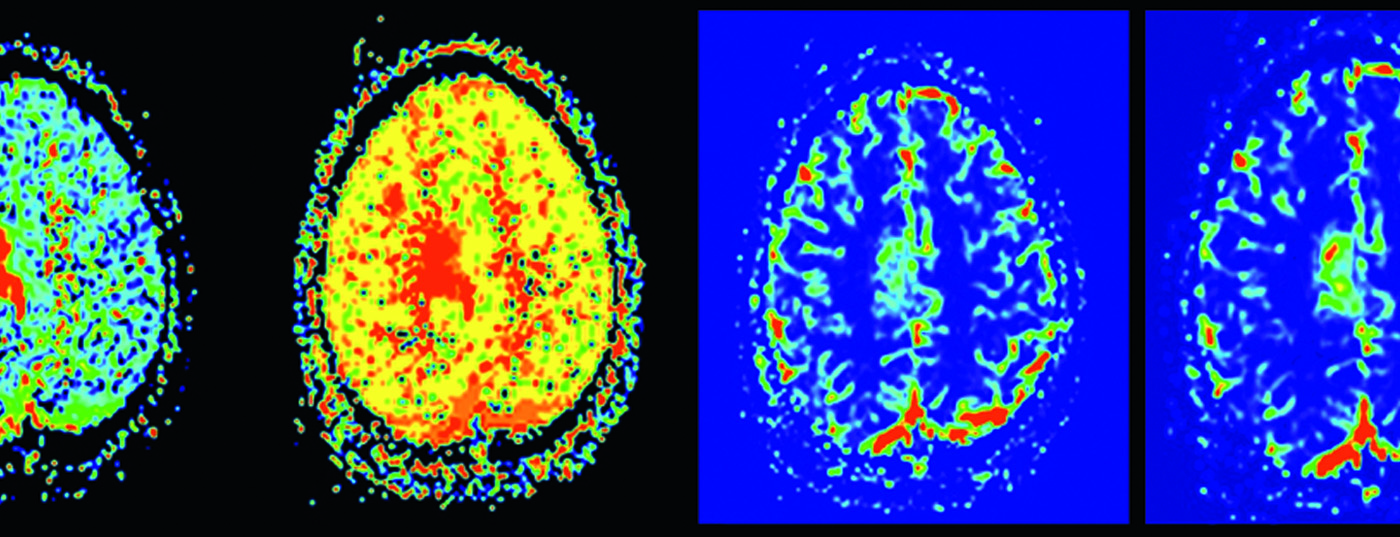

Fallbericht: Ein 30-jähriger Mann mit unauffälliger medizinischer Vorgeschichte erlitt einen fokalen klonischen Anfall der linken oberen Extremität, sekundär generalisiert. Fünf Tage zuvor hatte der Patient Fieber (38,6°) mit Erkältungssymptomen. Die körperliche Untersuchung war abgesehen von einem Zungenbiss unauffällig, das EEG normal. Die Liquorpunktion zeigte eine lymphozytäre Pleozytose, normale Glukosewerte und gering erhöhtes Protein.